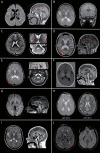

Results: We evaluated 126 patients (101 children and 25 adults) with ages ranging from 1 month to 74 years. We obtained a first molecular diagnosis by singleton WES in 59% of cases, which increased to 68% after annual reanalysis, and reached 72% after WGS was performed in 16 of the remaining negative cases. We identified variants in 57 different genes among 91 diagnosed cases, with the most frequent being RNASEH2B, EIF2B5, POLR3A, and PLP1, and a dual diagnosis underlying complex phenotypes in 6 families, underscoring the importance of genomic analysis to solve these cases. We discovered 9 candidate genes causing novel diseases and propose additional putative novel candidate genes for yet-to-be discovered GWMD.

Figures